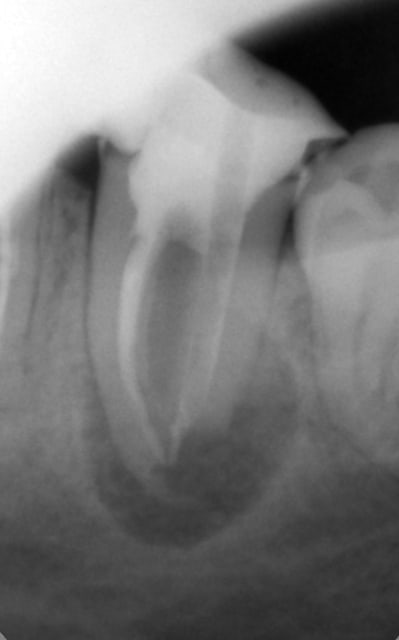

encore des radios,peut-etre assez moyen comme traitement...mais je vu pire...

les dernieres radios. patient en urgence ,abces... il voulait pas extraire la dent. j'ai lui bien explque et il a choisi de essayer de garder la dent. retrait,pas d'isolation avec la digue donc pas de tenon fibree,amalgam et screw post.traitement fait il ya 2 ans je crois.patient fidel de cabinet maintenent.

j'ai jamais utilise en roumanie l'amalgam et ca s'utilise pas du tout dans le cabinet du roumanie.